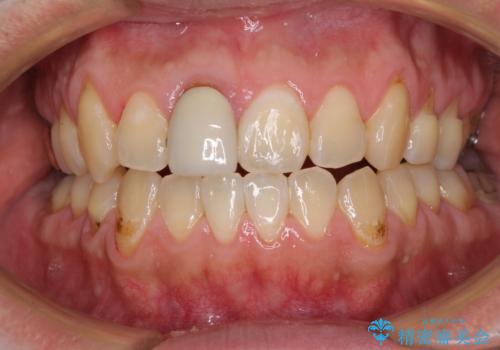

前歯のデコボコとクロスバイトをインビザライン矯正で改善

- 前歯のデコボコと上下のクロスバイトを気にして来院された患者様です。

インビザラインを用い、IPR(歯と歯の間を削る)と歯列全体を拡大させることで、歯並びを整えていくこととしました。